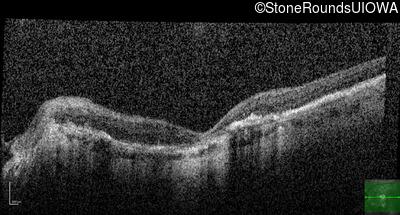

Optical Coherence Tomography - Right - 20/200 +2

Exemplar / OCT Stack